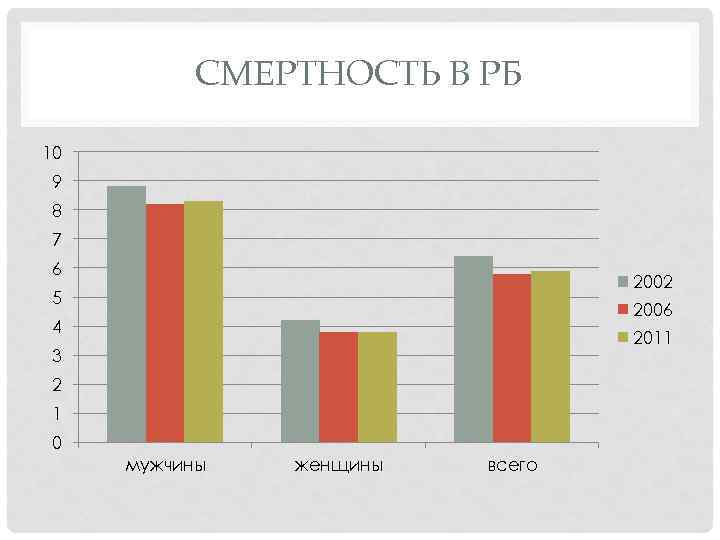

СМЕРТНОСТЬ В РБ 10 9 8 7 6 2002 5 2006 4 2011 3 2 1 0 мужчины женщины всего

СМЕРТНОСТЬ В РБ • Одногодичная летальность для всего населения была 19, 4%, у мужчин – 22, 2%, у женщин – 15, 0%. • Соотношение смертности и заболеваемости раком почки выглядело следующим образом: 0, 34 – среди всего населения, 0, 38 – у мужчин, 0, 28 – у женщин.